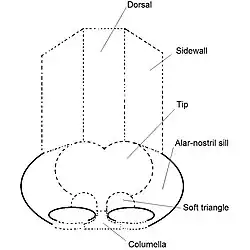

To plan, map, and execute the surgical correction of a nasal defect or deformity, the structure of the external nose is divided into nine aesthetic nasal subunits, and six aesthetic nasal segments, which provide the plastic surgeon with the measures for determining the size, extent, and topographic locale of the nasal defect or deformity.

The surgical nose as nine aesthetic nasal subunits

- tip subunit

- columellar subunit

- right alar base subunit

- right alar wall subunit

- left alar wall subunit

- left alar base subunit

- dorsal subunit

- right dorsal wall subunit

- left dorsal wall subunit

In turn, the nine aesthetic nasal subunits are configured as six aesthetic nasal segments; each segment comprehends a nasal area greater than that comprehended by a nasal subunit.

The surgical nose as six aesthetic nasal segments

- the dorsal nasal segment

- the lateral nasal-wall segments

- the hemi-lobule segment

- the soft-tissue triangle segments

- the alar segments

- the columellar segment

Using the co-ordinates of the subunits and segments to determine the topographic location of the defect on the nose, the plastic surgeon plans, maps, and executes a rhinoplasty procedure. The unitary division of the nasal topography permits minimal, but precise, cutting, and maximal corrective-tissue coverage, to produce a functional nose of proportionate size, contour, and appearance for the patient. Hence, if more than 50 percent of an aesthetic subunit is lost (damaged, defective, destroyed) the surgeon replaces the entire aesthetic segment, usually with a regional tissue graft, harvested from either the face or the head, or with a tissue graft harvested from elsewhere on the patient's body.[21]

External nasal anatomy

The form of the nasal subunits—the dorsum, the sidewalls, the lobule, the soft triangles, the alae, and the columella—are configured differently, according to the race and the ethnic group of the patient, thus the nasal physiognomies denominated as: African, platyrrhine (flat, wide nose); Asiatic, subplatyrrhine (low, wide nose); Caucasian, leptorrhine (narrow nose); and Hispanic, paraleptorrhine (narrow-sided nose). The respective external nasal valve of each nose is variably dependent upon the size, shape, and strength of the lower lateral cartilage.[22]

Nasal analysis

The surgical management of nasal defects and deformities divides the nose into six anatomic subunits: (i) the dorsum, (ii) the sidewalls (paired), (iii) the hemilobules (paired), (iv) the soft triangles (paired), (v) the alae (paired), and (vi) the columella. Surgical correction and reconstruction comprehend the entire anatomic subunit affected by the defect (wound) or deformity, thus, the entire subunit is corrected, especially when the resection (cutting) of the defect encompasses more than 50 percent of the subunit. Aesthetically, the nose—from the nasion (the midpoint of the nasofrontal junction) to the columella-labial junction—ideally occupies one-third of the vertical dimension of the person's face; and, from ala to ala, it ideally should occupy one-fifth of the horizontal dimension of the person's face.[23]

The nasofrontal angle, intersection of the line from the nasion to the nasal tip with the line from the nasion to the glabella, usually is 115-130 degrees; the nasofrontal angle is more acute in the male face than in the female face. The nasofacial angle, intersection of the line from the nasion to the nasal tip with the line from the nasion to the pogonion, is approximately 30–40 degrees. The nasolabial angle, the slope between the columella and the philtrum, is approximately 90–95 degrees in the male face, and approximately 100–105 degrees in the female face. Therefore, when observing the nose in profile, the normal show of the columella (the height of the visible nasal aperture) is 2 mm; and the dorsum should be rectilinear (straight). When observed from below (worm's-eye view), the alar base configures an isosceles triangle, with its apex at the infra-tip lobule, immediately beneath the tip of the nose. The facially proportionate projection of the nasal tip (the distance of the nose's tip from the face) is determined with the Goode Method, wherein the projection of the nasal tip should be 55–60 percent of the distance between the nasion (nasofrontal junction) and the tip-defining point. A columellar double break might be present, marking the transition between the intermediate crus of the lower-lateral cartilage and the medial crus.